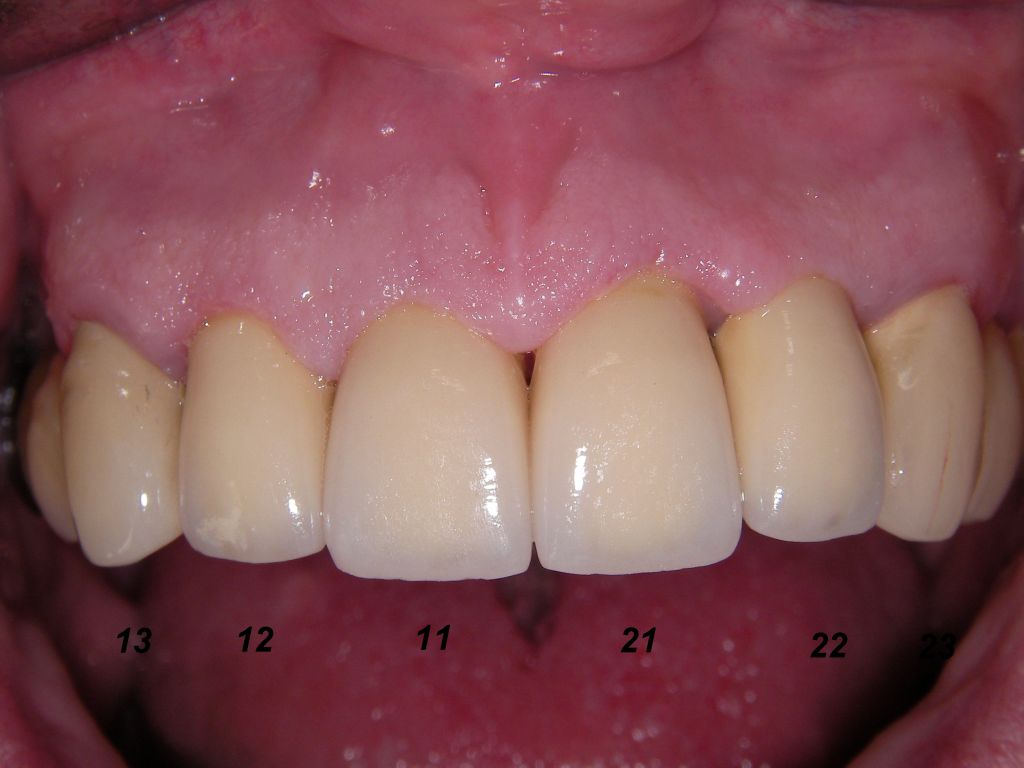

Links die Kronen aus dem Dentallabor "Heitmeyer Zahntechnik", Osnabrück. Man sieht praktisch keinen Metallrand. Der Patient war zur Farbbestimmung im Dentallabor - so halten wir es praktisch immer. Rechts das Ergebnis bei der 1. Nachkontrolle am 27.3.05. Das Zahnfleisch muß sich noch etwas erholen.